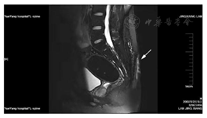

患者血常规、肝肾功能、凝血功能未见明显异常。入院前2周,骶尾部增强MRI提示尾椎后方皮下见条片状异常信号,大小约108×16mm,T1WI呈稍低信号,T2WI呈混杂高信号,病灶与皮肤相通,增强后见实性部分呈较明显强化。扫描范围内肛管未见明显异常。诊断:尾椎后方皮下藏毛囊肿并感染,请结合临床(图2)。